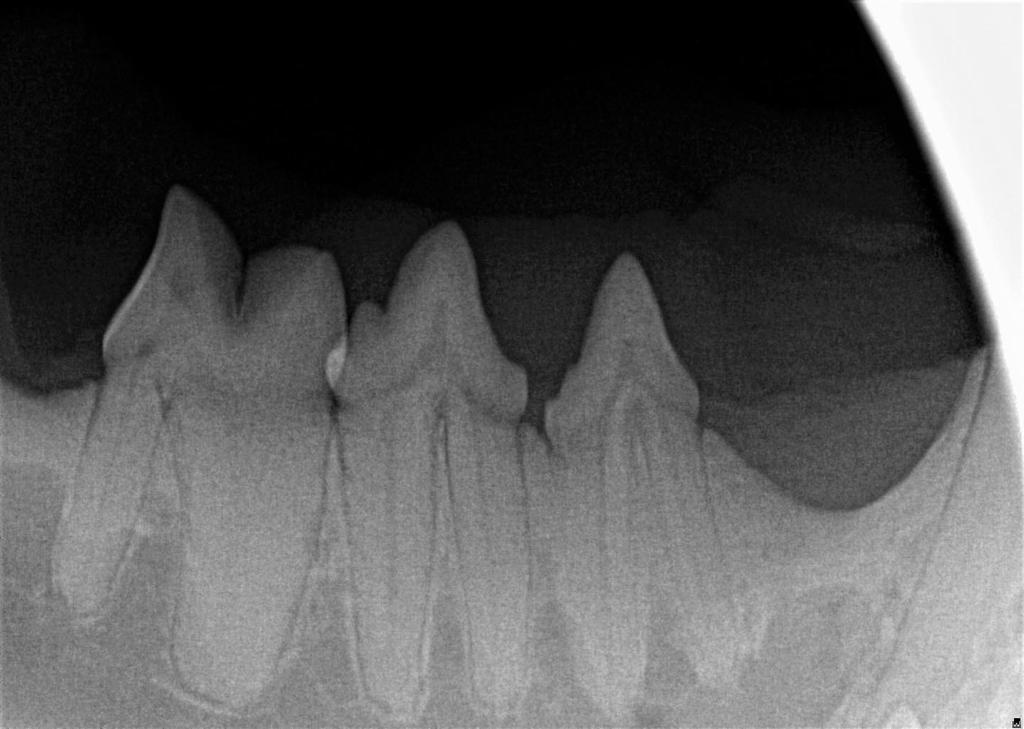

The visible part of the tooth that sits above the gumline is called the crown. However, up to 75% of the tooth structure is below the gumline – the root, periodontal ligament and pulp cavity are all not visible to us without a dental X-Ray.

Dental X-Rays are especially important in feline dentistry. This is because cats very commonly get a disease called tooth resorption, where cells called odontoclasts destroy and dissolve the tooth, later replacing it with bone. This is a painful and irreversible disease and the only treatment is extraction of the affected teeth. Because the disease starts with the tooth root below the gumline and only starts affecting the visible crown of the tooth much later in the disease process, we cannot know which teeth are affected without taking radiographs.

Below shows an image of a normal tooth on dental X-Ray compared to a tooth that is undergoing tooth resorption in the three images below the main one.

Dental X-Rays can also be used in a number of other situations, including to assess for pulp necrosis, periodontal disease, jaw fractures and retained root fragments.